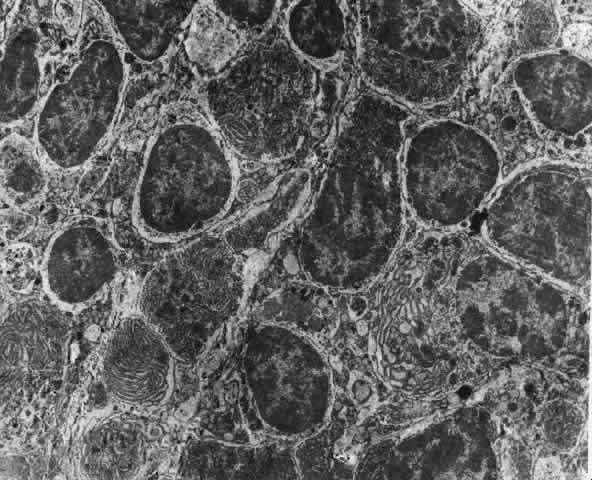

What is clinically represented solely by inflammation and edema is histopathologically a granulomatous lesion of the sclera, the center of which consists largely of plasma cells, lymphocytes, and mast cells (Figs. 21 through 23). Foster and colleagues have identified the cellular subsets and glycoproteins in both necrotizing and non-necrotizing scleritis.22 This shows an active T-cell inflammatory response with a high CD4/CD8 ratio and increased HLA/DR and CD14, indicating a macrophage-induced response that would lead to granuloma formation. Remote from the granuloma, the fibrocytes of the sclera become activated, the proteoglycan adjacent to them becomes altered, and the collagen fibrils of the sclera become unraveled (Figs. 23 and 24). These changes appear to take place prior to the invasion of the stroma by cells of the granuloma.20 The vessels in and around the necrotic area show medial necrosis and perivascular cuffing with lymphocytes, and endothelial swelling with microvascular occlusion. Ninety-six percent of the specimens examined by Foster and associates show a microangiopathy characterized by a neutrophil infiltrate in and around the vessel wall.22–23 This is most obvious at the center of the lesion where there may be occlusion of the vessel, thrombosis, or even aneurysm formation (Fig. 25). From these pathologic investigations, clinical observations, animal experiments, and the results of fluorescein angiography, it would appear that the scleral inflammation is initiated either by trauma (be it accidental or surgical)23–25 or by bacterial or viral infection. If circulating immune complexes are present because of the poor blood flow, they become precipitated in and around the vessel walls in the area of inflammation. In other patients, a persistence of tissue damage will lead to autoimmunization. Damage to the endothelial cells of the microvasculature leads to changes within the vessels detectable on angiography and to catabolic changes in the surrounding tissues. These changes, in turn, allow the granulomatous response that is seen in histopathologic sections, the first detectable change being in the scleral fibrocytes and the proteoglycan and collagen remote from the site of cellular infiltration.

Fig. 22. Electron micrograph of an area of active scleritis showing the plasma cell infiltrate suggestive of an immune response. Note aggregated plasma cells, with the characteristic whorled rough endoplasmic reticulum, in the process of degeneration, releasing organelles and nuclear debris into the extracellular matrix. (Uranyl acetate and lead citrate. X3000) (Courtesy of Dr. R. Tripathi)

Fig. 23. Electron micrographs of scleral stroma at the periphery of an area of ulceration in a patient with necrotizing scleritis. The left shows an active fibroblastic cell, and the right shows collagen fibrils within intracellular vacuoles (V) in the fibroblastic cell. (Left X15,375; right X15,375) (Watson PG, Young RD: Changes at the periphery of a lesion necrotizing scleritis: Anterior segment fluorescein angiography correlated with electron microscopy. Br J Ophthalmol 68:781–789, 1984)

Fig. 24. Electron micrograph of scleral stroma at the periphery of an ulcer in necrotizing scleritis (same patient as in Figure 23) showing swelling and unraveling of collagen fibrils (arrows) in longitudinal section (X29,270) and in transverse section (inset, X44,000). Fibrils of all diameters are affected. (Watson PG, Young RD: Changes at the periphery of a lesion necrotizing scleritis: Anterior segment fluorescein angiography correlated with electron microscopy. Br J Ophthalmol 69:656–663, 1985)